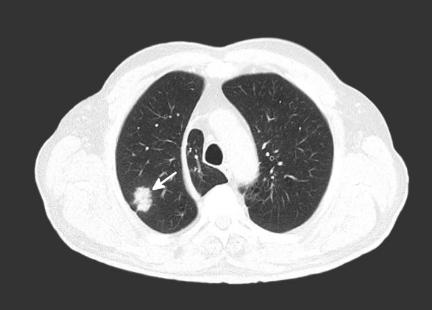

侵袭性真菌病肺部影像学表现(真菌感染区呈现团块状高密度阴影)(图片来源:veer图库)